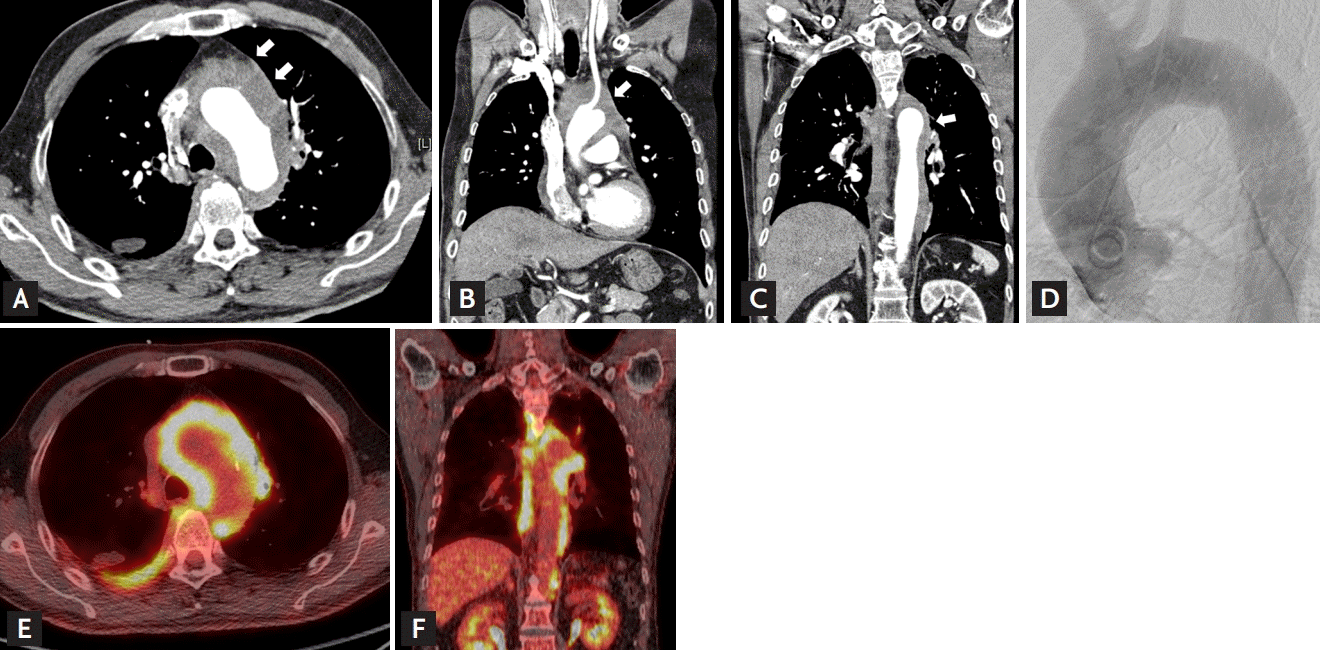

A 68-year-old man was referred to our hospital owing to dyspnea and a low-attenuation mass-like lesion encasing the aortic arch extending to the descending thoracic aorta observed on chest computed tomography (CT) (Fig. 1A-1C).

Transthoracic echocardiogram and coronary angiography, including an aortogram, revealed no specific dyspnea-related findings (Fig. 1D). Additional laboratory tests were conducted for the differential diagnosis of infective diseases, rheumatologic diseases, hematologic diseases, and other malignancies.

Positron emission tomography showed intense fluorodeoxyglucose uptake in the mediastinal soft tissue infiltrative lesion (Fig. 1E and 1F). Incisional biopsy was performed (Fig. 2A and 2B). Pathological analysis revealed lymphoplasmacytic infiltration with fibrosis and an elevated IgG4 level (64 cells/high-power field) and IgG4/IgG ratio (82%), suggestive of IgG4-related periaortitis (Fig. 2C and 2D).

Figure 1.

Imaging study. (A, B, C) Aorta computed tomography (CT) images showing a low-attenuation mass-like lesion encasing the aortic arch extending to the descending thoracic aorta (arrows). (D) Aortogram showing absence of significant luminal narrowing. (E, F) Positron emission tomography-CT image showing intense fluorodeoxyglucose uptake in the mediastinal soft tissue infiltrative lesion, involving the aortic arch and extending to the abdominal aorta, and right posterior pleural thickening.